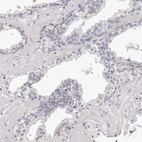

Immunohistochemistry analysis in human placenta and prostate tissues using Anti-PEG10 antibody. Corresponding PEG10 RNA-seq data are presented for the same tissues.